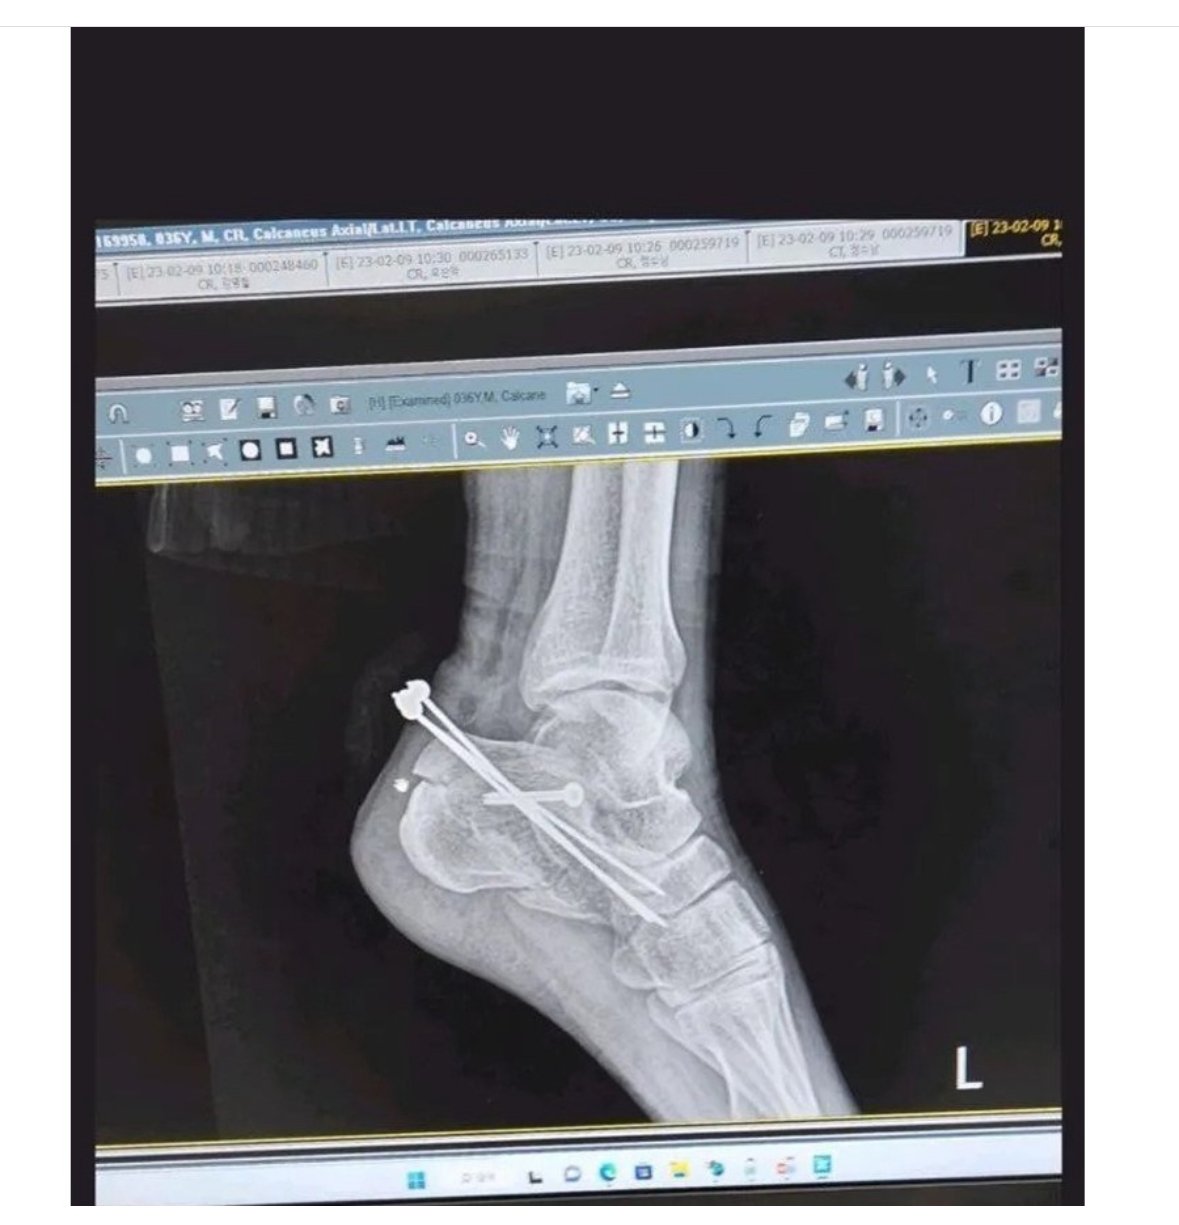

[스크랩] 관우도 계집애처럼 소리지를 집에서 손으로 철심 뺀 사람..JPG 작성자야바위 라이토|작성시간24.04.04|조회수396 목록 댓글 0 글자크기 작게가 글자크기 크게가 다음검색 스크랩 원문 : 도탁스 (DOTAX) 현재 게시글 추가 기능 열기 북마크 공유하기 신고 센터로 신고 댓글 댓글 0 댓글쓰기 답글쓰기 댓글 리스트